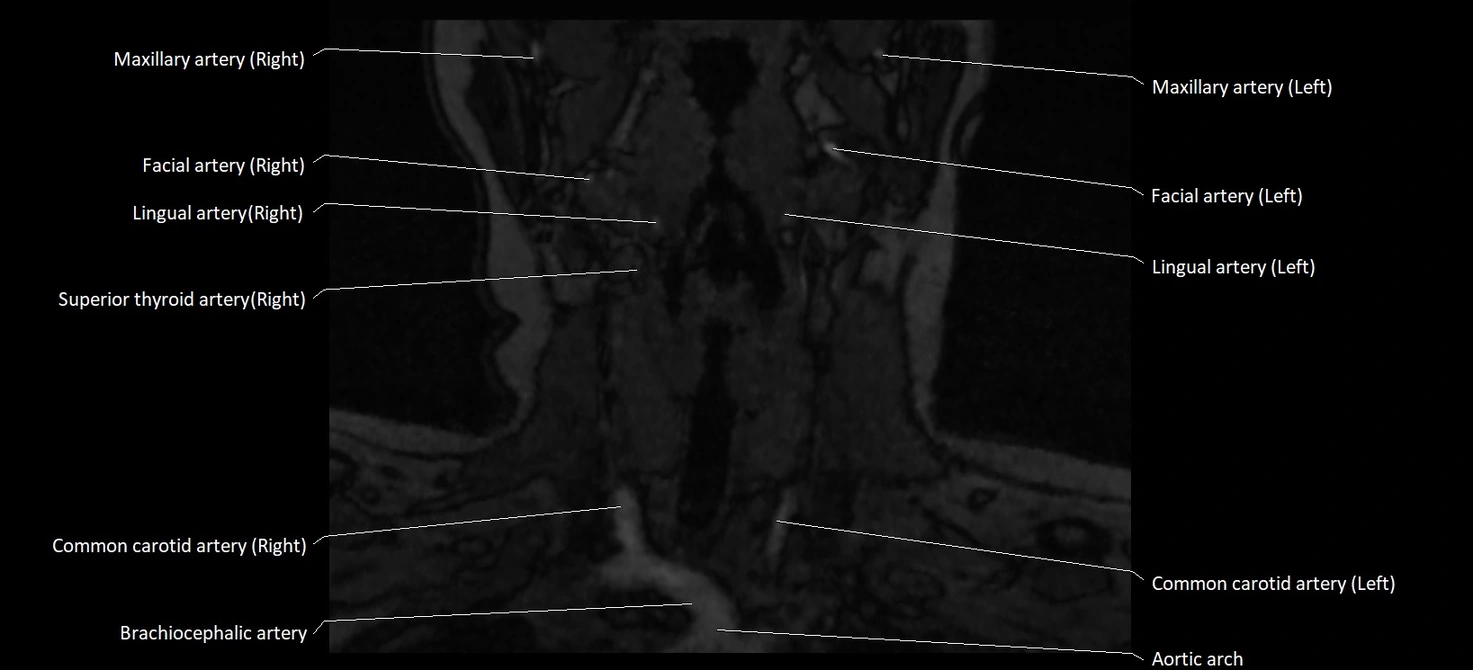

CT image

image